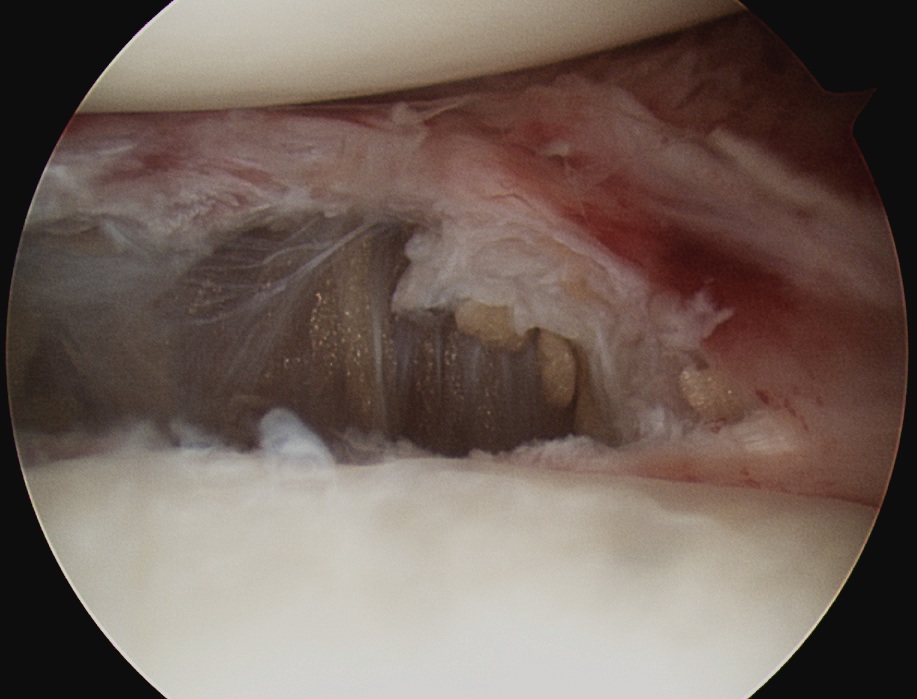

Release rotator interval - remove all tissue in between biceps and SSC

Mobilze subscapularis front and back from scar tissue

Release anterior IGHL from 3 to 5 o'clock, leaving labrum intact

Rotator interval release

Release anterior IGHL